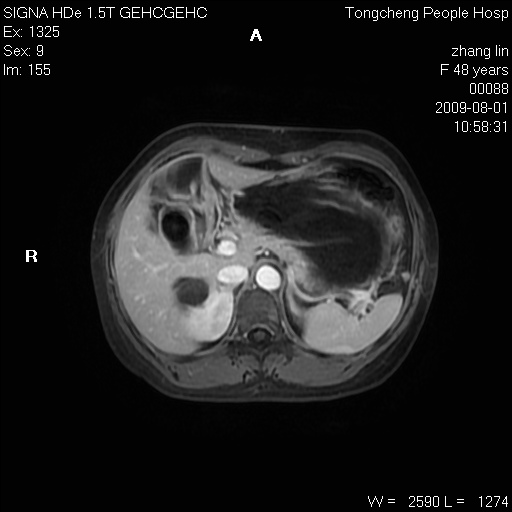

女,48岁。健康体检,彩超发现右肾占位性病变。平素健康。

临床诊断:右肾占位性病变,性质待定(囊肿?肿瘤?)。

上中腹部mr平扫+增强扫描,图像如下:

右肾上极见一类圆形病灶,t1wi呈等信号t2wi呈等高混杂信号,三期增强无强化,边界清---考虑囊肿出血。

同反相位均表现为等信号,病变无强化,考虑含蛋白的囊肿可能,弥散加权相或许有些帮助,

肝囊肿

慢性胆囊炎